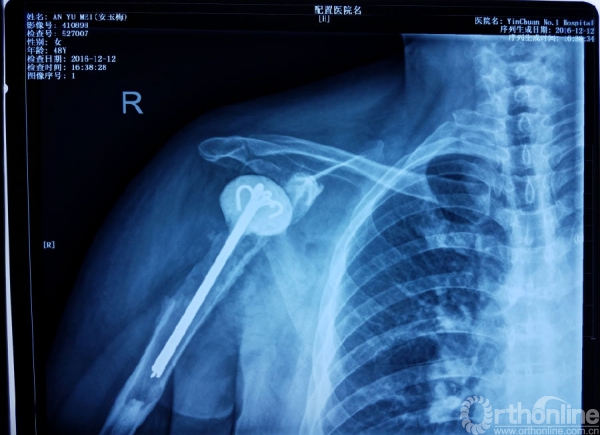

患者主诉:行右肩关节置换术后11年,发现腋窝红肿疼痛2月入院。

专科检查:痛苦面容,右肩被动体位;

位于右肩前方见陈旧性手术切口;

切口位于腋前线处局部皮肤红肿,皮温高于左侧,并可见窦道形成,有少许淡黄色分泌物溢出。

体格检查:

触诊:肩关节饱满,僵硬,位于肩峰及三角肌外侧压痛明显。以切口周围疼痛最为剧烈。

关节活动:

主动上举30°被动上举30°

主动外旋10°外展20°

主动内旋拇指尖位于骶尾部水平

主动内收30°

二次入院时情况

抗生素使用2周,局部换药后

二次入院核磁检查

二次入院时X线检查

术后X线